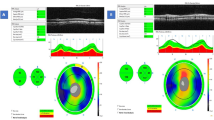

We developed a customized software (Anterior Segment Analysis Program (ASAP)) to measure pRNFL parameters, including thickness and grayscale value automatically5. ASAP was coded as a plug-in software under ImageJ (version 1.38x), a public domain Java program (available at http://rsb.info.nih.gov/ij, National Institutes of Health, Bethesda, MD, USA). The software first automatically detected the pRNFL and RPE's boundary. One ophthalmologist (XL.X with five years of experiments) inspected every OCT image and excluded images with boundary misidentification. The detail of grayscale value had been reported by other research groups and us. In this study, the grayscale value was defined as the gray value range from 0 (pure black) to 255 (pure white). The ASAP software then automatically calculated the pRNFL parameters on average and six different sectors after automatically delineating retinal structure boundary, like pRNFL and RPE. pRNFL parameters evaluated in this study were the average thickness and grayscale value in 360°, with 315°–45° position designated temporal, 270°–315° position inferior temporal, 225°–270° position inferior nasal, 135°–225° position nasal, 90°–135° position superior nasal and 45°–90° position superior temporal (Fig. 1). A subset of 20 images was randomly selected for assessing the inter-observer reproducibility. 2 examiners (X.L and C.Z) independently measured pRNFL parameters using ASAP. The intra-class correlation coefficient ranged from 0.74 to 0.95 for all the pRNFL measurements in the current study.

The mean and SD of the pRNFL parameters of each age group are summarized in Table 2. The mean average of pRNFL grayscale value and thickness 164.82 ± 5.69 and 106.68 ± 8.89 μm, respectively. pRNFL grayscale value in nasal sectors (163.26 ± 9.31) was significantly lower comparing those in all other five sectors (all with p < 0.001, statistically significant after Bonferroni correction)] (Fig. 2). Table 3 shows the univariable analysis of the demographic characteristics and ocular features associated with pRNFL grayscale value and thickness. A lower average pRNFL grayscale value was significantly correlated with older age (β = − 0.370, p < 0.001) (Fig. 3), male (β = − 0.155, p = 0.002), better best corrected visual acuity ((β = − 0.294, p < 0.001), thinner pRNFL thickness (β = 0.257, p < 0.001), lower RPE grayscale value (β = 0.284, p < 0.001) (Fig. 4) and lower ImageQ (β = 0.575, p < 0.001) (Fig. 5). The significant parameters in univariable regression carried forward for multivariable analysis. As previous studies have shown that axial length correlated with pRNFL thickness11, we therefore added axial length in multivariable analysis as well. Table 4 shows multivariable analysis of pRNFL grayscale value after adjustment of associated factors. A lower average pRNFL grayscale value was independently correlated to older age (β = − 0.053, p = 0.002), l onger axial length (β = − 0.664, p = 0.003), lower RPE grayscale value (β = 0.372, p < 0.001) and lower ImageQ (β = 0.658, p < 0.001) (Fig. 6).